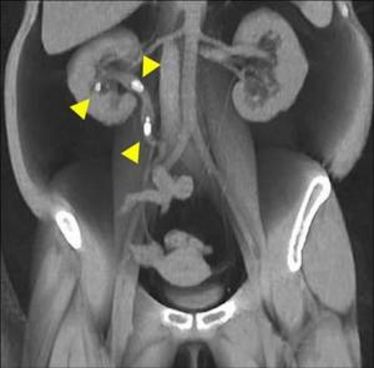

5. Münsteraner Andrologie-Update 2013

5. Münsteraner Andrologie-Update 2013